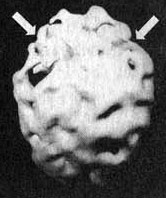

Мозг Эллен — последствия инсульта ![]() Трехмерное изображение поверхности мозга, вид слева. Обратите внимание на обширную «дыру», сформировавшуюся в результате инсульта в левой лобной доле 2. SPECT позволяет дать точную оценку состояния пациента, позволяющую предотвратить, заболевание в будущем. Нэнси, 59 лет, страдала от тяжелой депрессии, не поддававшейся лечению. Поступила в психиатрическую лечебницу, где ей было проведено исследование SРЕСТ. Каково же было мое удивление, когда оказалось, что в прошлом, при полном отсутствии соответствующих симптомов, она перенесла два обширных инсульта. Таким образом, стало понятно, что вызвало эту депрессию, не поддававшуюся обычному лечению. У 60 % пациентов, перенесших кровоизлияние во фронтальных долях, через год развивается тяжелая депрессия. Получив результаты SPECT, я немедленно проконсультировался с неврологом, который постарался определить причины инсультов, к которым нередко приводят, скажем, бляшки в сонных артериях или сердечная аритмия. Он пришел к выводу, что причиной инсультов у Нэнси стали тромбы, и назначил ей препараты, снижающие вязкость крови, чтобы предотвратить развитие новых инсультов. Мозг Нэнси — последствия двух инсультов ![]() Трехмерное изображение поверхности, вид сверху ![]() Трехмерное изображение поверхности, вид справа 3. С помощью SPECT можно получить информацию, помогающую врачу добиться понимания и сострадания к пациенту у членов его семьи. Фрэнк — состоятельный, хорошо образованный человек. Вскоре после того как ему исполнилось 70 лет, он стал забывчивым. Сначала он забывал мелочи, но со временем провалы в памяти стали прогрессировать, и он начал забывать значимые факты собственной биографии: где он живет, как зовут его жену и даже как зовут его самого. Жена и дети были не в состоянии понять, чем вызваны такие перемены, а его рассеянность и забывчивость их нередко раздражали. Результаты SPECT показали, что у Фрэнка на всей поверхности мозга отмечается резкое снижение активности, и особенно во фронтальных, париетальных и височных долях. Это была классическая картина синдрома Альцгеймера. Показав семье снимки и объяснив, что забывчивость Фрэнка имеет четкую физиологическую природу, я помог им осознать, что он не специально раздражает их, а серьезно болен. Впоследствии, вместо того чтобы упрекать его за забывчивость, близкие Фрэнка стали поддерживать его и разработали схемы, позволившие эффективнее бороться с трудностями, возникающими у всякого, кто вынужден жить рядом с человеком, страдающим болезнью Альцгеймера. Мозг Фрэнка — болезнь Альцгеймера ![]() Трехмерное изображение поверхности, вид сверху ![]() Трехмерное изображение нижней поверхности Обратите внимание на выраженное общее снижение активности, особенно в париетальных долях (см. стрелки, рис. слева) и в височных долях (см. стрелки, рис. справа). 4. SPECT позволяет проводить дифференциальную диагностику состояний со сходной симптоматикой. Я познакомился с Маргарет, когда ей было 68. Выглядела она неухоженно и неопрятно. Маргарет жила одна, и ее близких это очень беспокоило, так как у нее появились симптомы тяжелой деменции. После того как она чуть не сожгла дом, оставив включенной плиту, ее поместили в психиатрическую клинику, где в то время работал я. Из общения с ее близкими обнаружилось, что Маргарет часто забывала, как зовут ее собственных детей, и нередко, ведя машину, сбивалась с дороги и оказывалась в незнакомом месте. Водительские навыки ухудшились настолько, что после четырех небольших ДТП всёго за шесть месяцев у нее отобрали права. К тому времени, когда я встретился с ее близкими, многих из них эта ситуация уже утомила, и они были готовы сдать Маргарет в специализированный приют. Другие были против такого решения и хотели бы сначала обследовать ее в условиях стационара. На первый взгляд казалось, что Маргарет страдает болезнью Альцгеймера. Однако по результатам SPECT обнаружилось, что активность мозга в париетальных и височных долях не нарушена. Если бы у нее был синдром Альцгеймера, кровоток в этих областях должен был бы быть снижен. Вместо этого единственной патологией, которую нам удалось обнаружить на снимках SPECT, стала зона повышенной активности в глубокой лимбической области в центре мозга. Такая картина часто наблюдается у пациентов, страдающих депрессией. Из-за схожей симптоматики у больных старшего возраста нередко бывает трудно дифференцировать депрессию и болезнь Альцгеймера. Тем не менее при псевдодеменции (депрессии, которая выглядит как слабоумие) человек может выглядеть слабоумным, на самом деле таковым не являясь. Это чрезвычайно важный момент, так как, диагностировав болезнь Альцгеймера, мы даем близким ряд специальных рекомендаций и назначаем пациенту некоторые медикаментозные средства. Между тем, диагностируя депрессию, мы проводим агрессивную медикаментозную терапию антидепрессантами в сочетании с психотерапией. Результаты обследования Маргарет убедили меня в том, что ей следует назначить антидепрессант Wellbutrin (бупропион). Всего три недели спустя она уже была разговорчивой, ухоженной и охотно общалась с другими пациентами. Через месяц после госпитализации ее выписали домой. Перед выпиской она попросила меня написать письмо в автоинспекцию с просьбой вернуть ей водительские права. Поскольку мы с ней ездим по одному и тому же шоссе, я заколебался. Я сказал ей, что, если улучшение будет стойким и сохранится на протяжении по меньшей мере полугода, а сама она станет придерживаться рекомендаций врача и принимать все лекарства, я напишу письмо в автоинспекцию. Через полгода она оставалась в хорошей форме. Я сделал повторный SPECT — результаты показали полную норму. Тогда я обратился в автоинспекцию, и ей вернули права. Мозг Маргарет — псевдодеменция ![]() Трехмерное изображение снизу — активный мозг, до лечения. ![]() Трехмерное изображение снизу активный мозг, после лечения. |